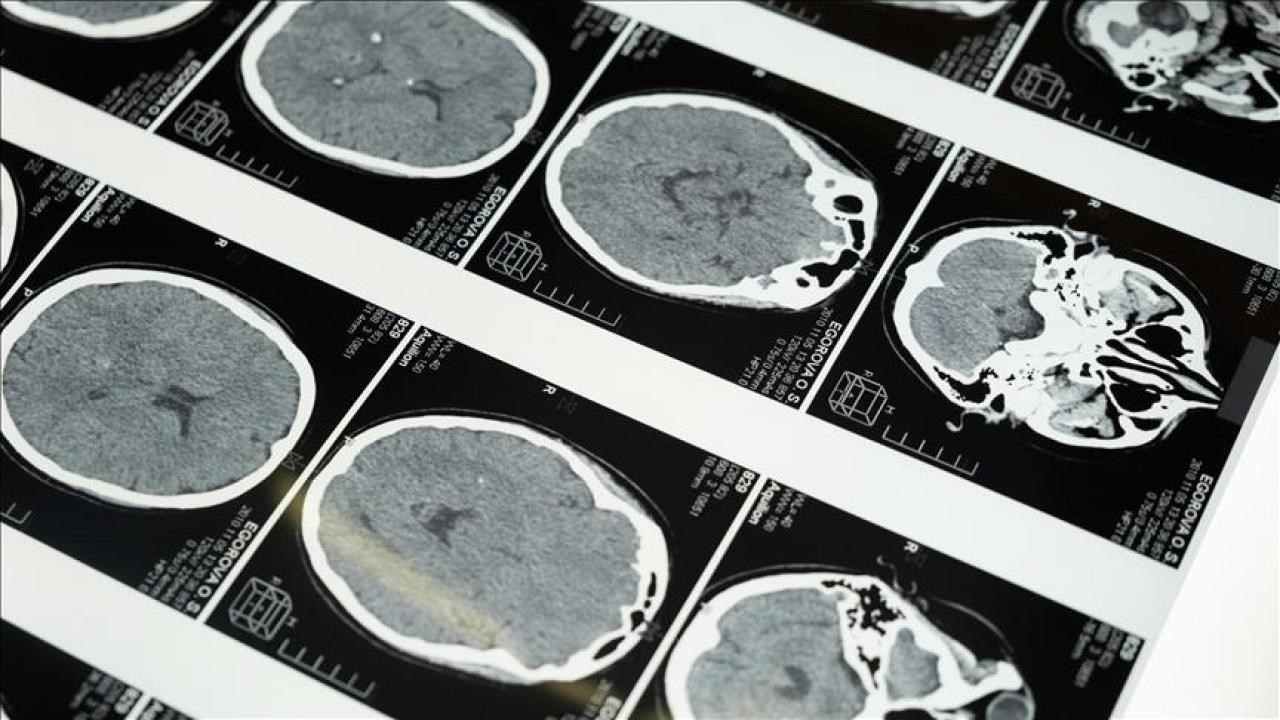

Uzmanlar, ehil olmayan kişilerce yapılan masajlar sırasında yırtılan damarın içinde oluşan pıhtının beyin damarlarını tıkayıp inmeye neden olabildiğini, özellikle gençlerde bu şekilde inme vakasının sıklıkla görüldüğünü bildirdi.